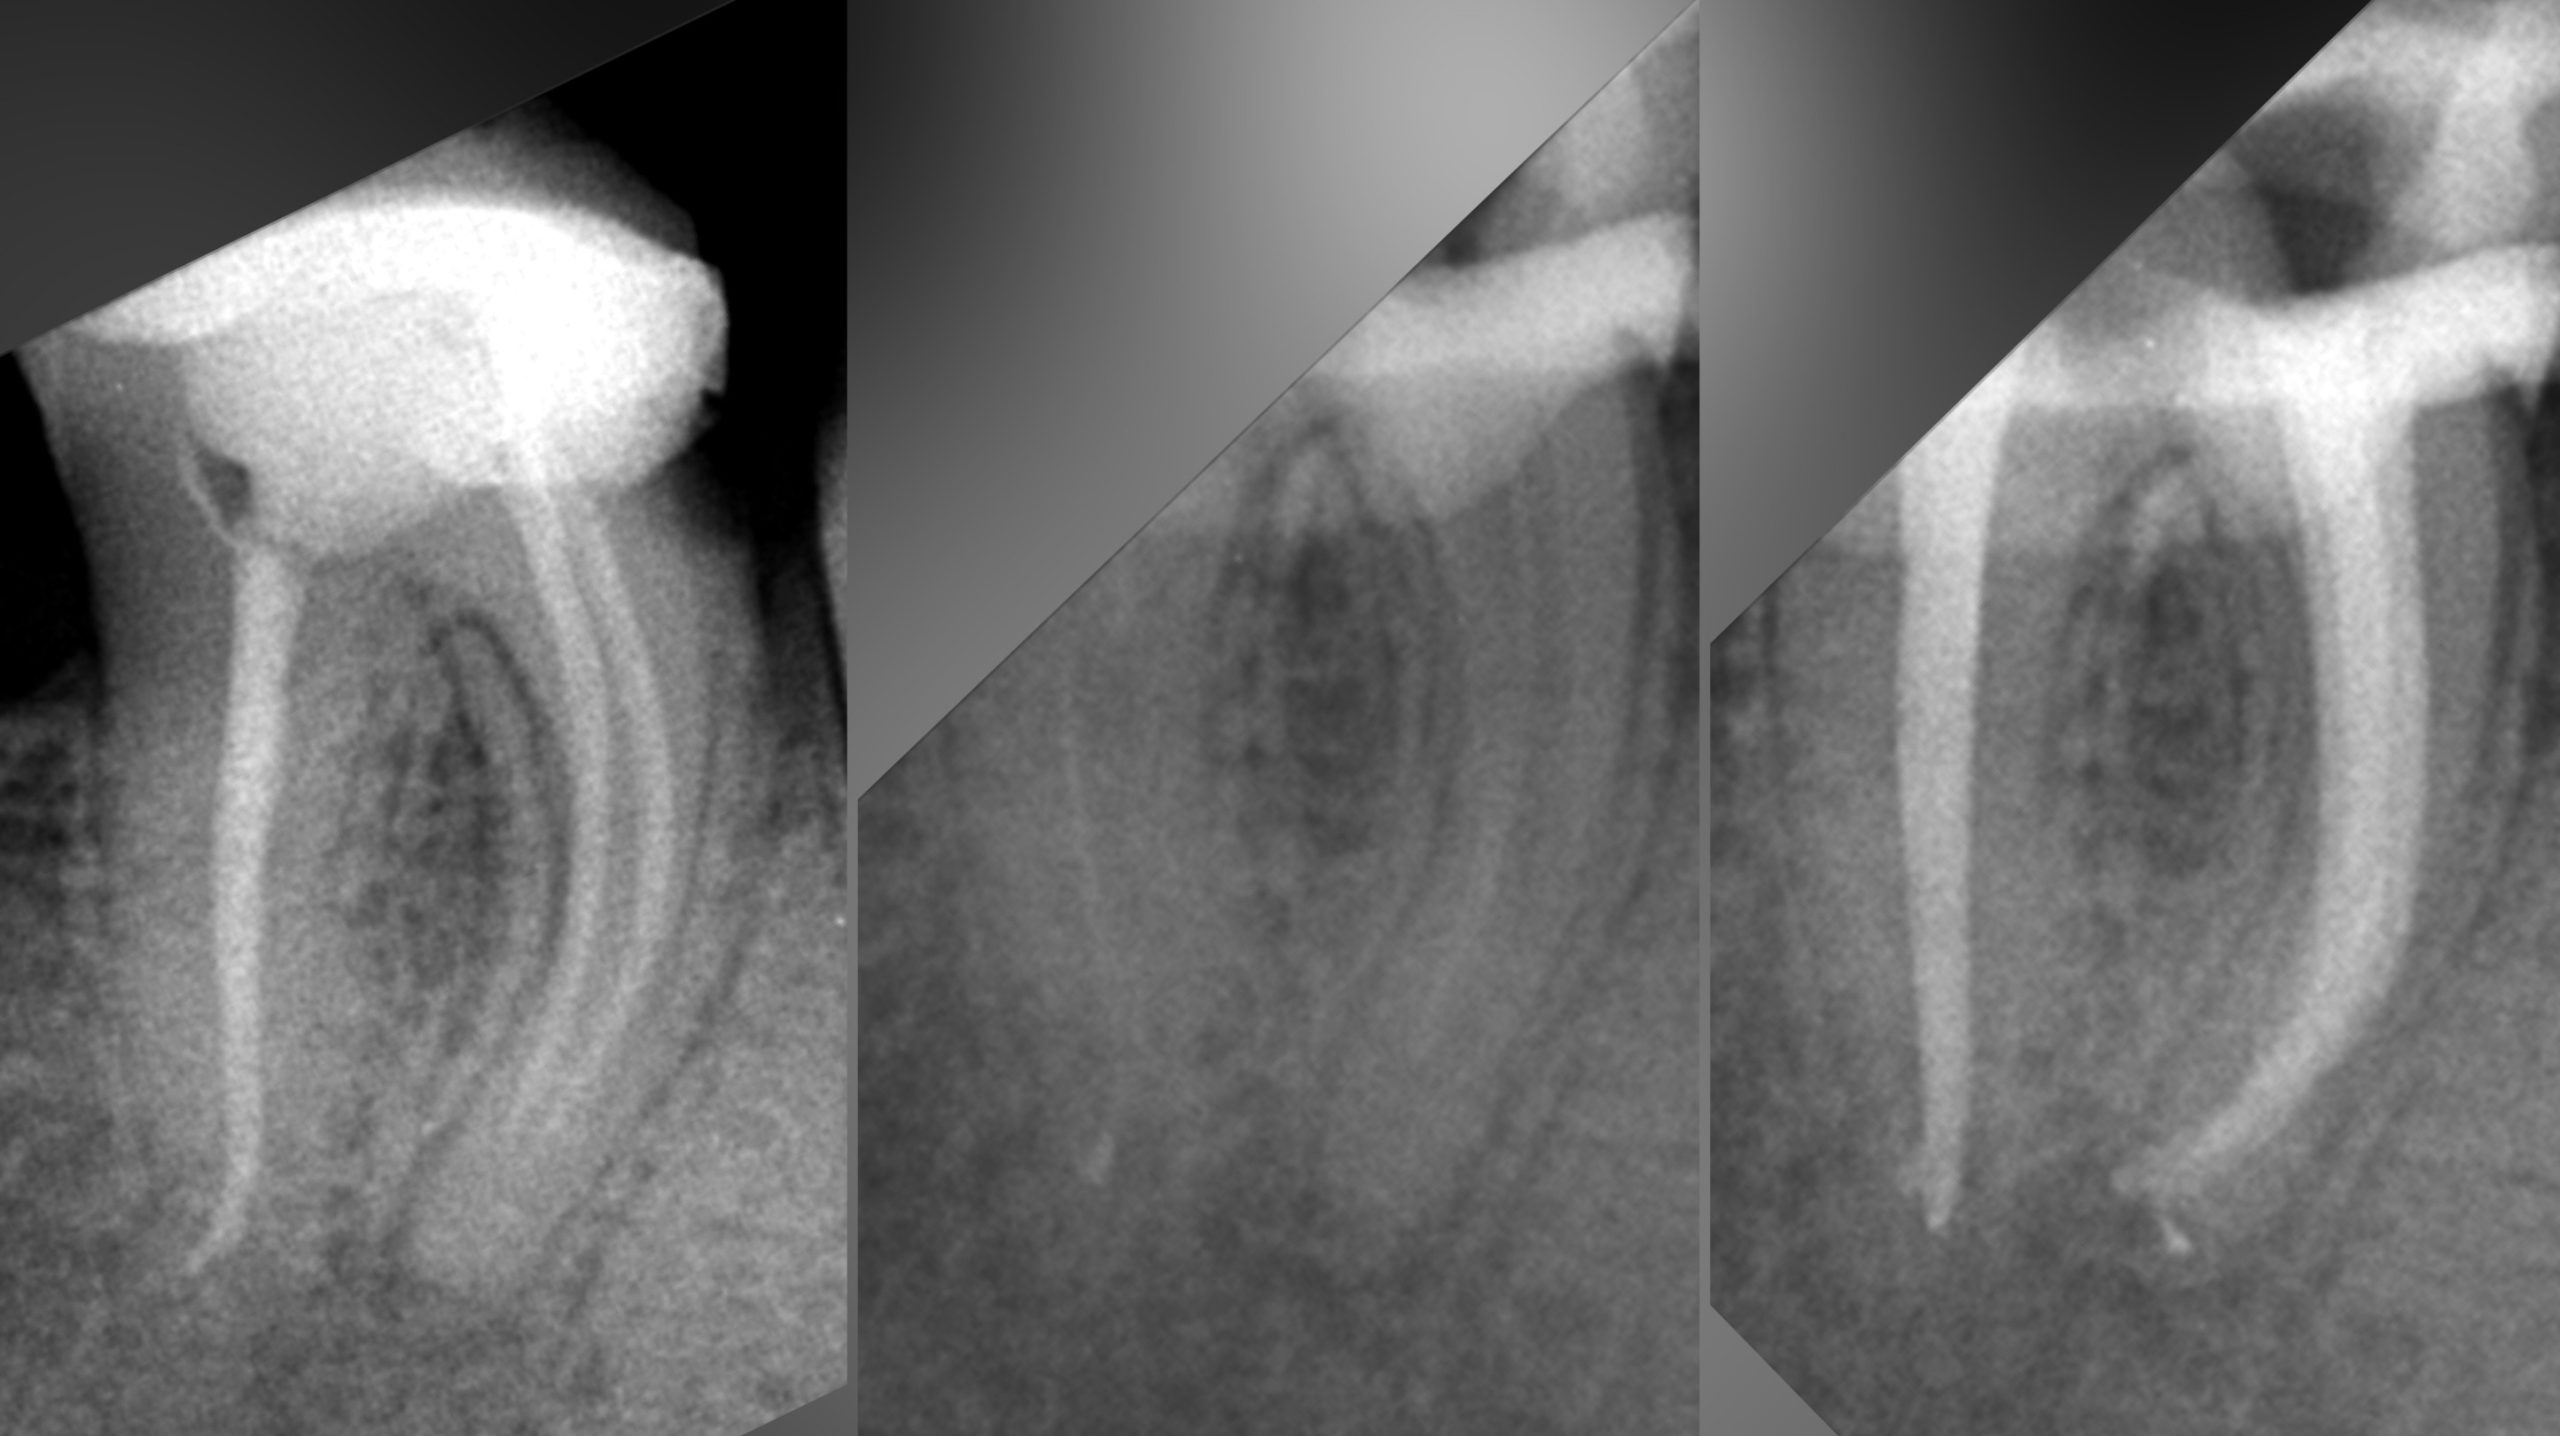

• Эндодонтическое лечение корневых каналов с использованием стоматологического микроскопа

2022 год – «Первичная эндодонтия с использованием современных клинических протоколов» Андрей Кольба

2023 год – «Первичная эндодонтия» Виталий Весна

2025 год – «Современные протоколы лечения эндодонтических пациентов» Dental Education Clinic,курс Елены

Драган